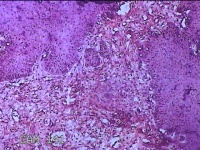

大腿内侧肿物

性别

女

年龄

47岁

临床诊断

纤维瘤病

一般病史

大腿内侧起丘疹四年余。

标本名称

大体所见

灰白暗红色肿物0.7x0.3x0.2cm一个,表面光滑,切开肿物呈实性,切面灰白粉红色,质软。